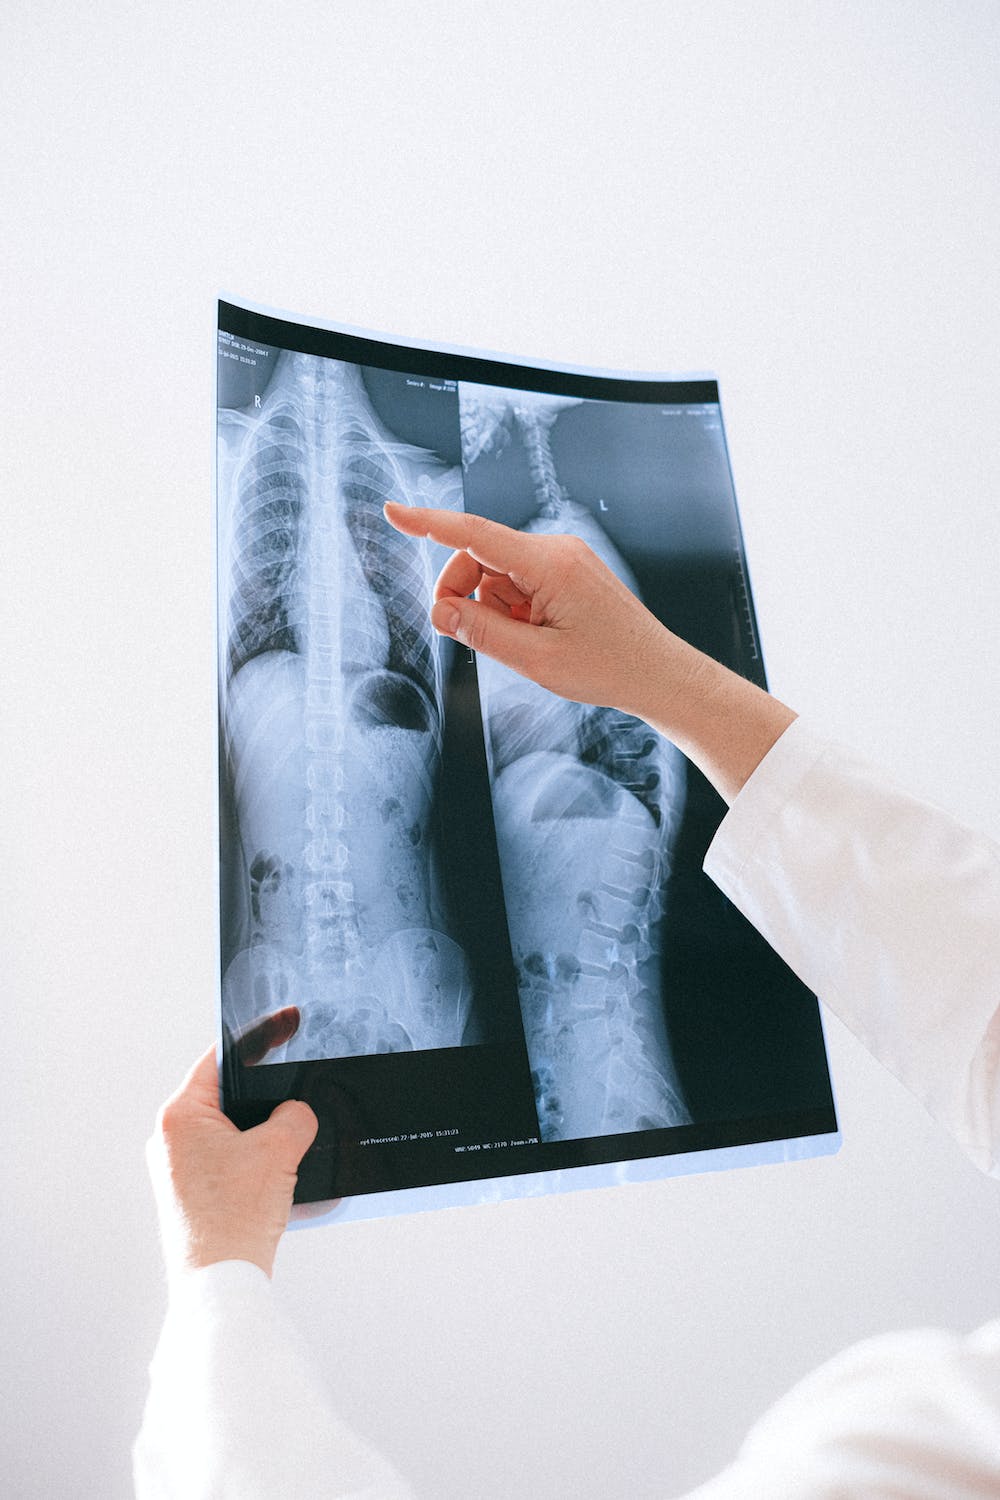

① 흉부 X선 촬영

X선 검사방법으로는 실제 크기로 촬영하는 흉부 직접촬영과 70㎜, 100㎜ 크기의 축소된 사진으로 찍는 간접촬영이 있는데, 여러 사람을 집단으로 검사할 경우에는 간접촬영을 많이 이용합니다.

소견에 따라 초감염 결핵과 재활성화 결핵으로 나뉘며 흔히 전자는 소아 결핵, 후자는 성인 결핵으로 분류하기도 하며 인체면역결핍 바이러스(HIV) 감염자는 초감염 결핵 소견이 주로 나타나는 것으로 알려져 있습니다.